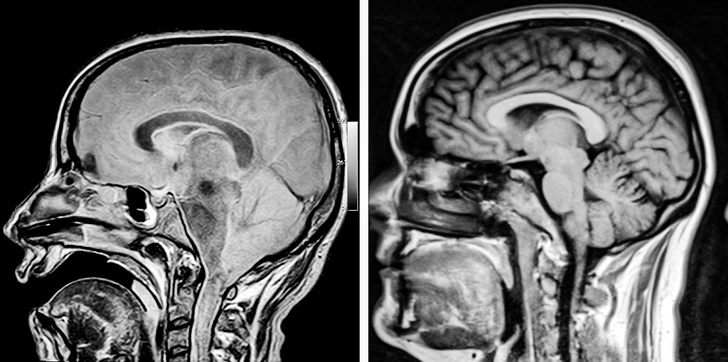

1. Мозок пацієнта в комі і мозок здорової людини

14. Пацієнт з алкогольним ураженням мозку. З-за впливу спиртних напоїв головний мозок і мозочок зменшилися в розмірах